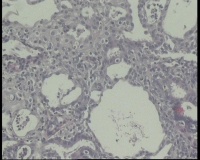

镜下见子宫内膜腺体异型增生,呈乳头状,筛网状排列,细胞核圆形,大小尚均匀,可见少量核分裂像,部分区域鳞化,间质少,部分区域无间质,间质有坏死